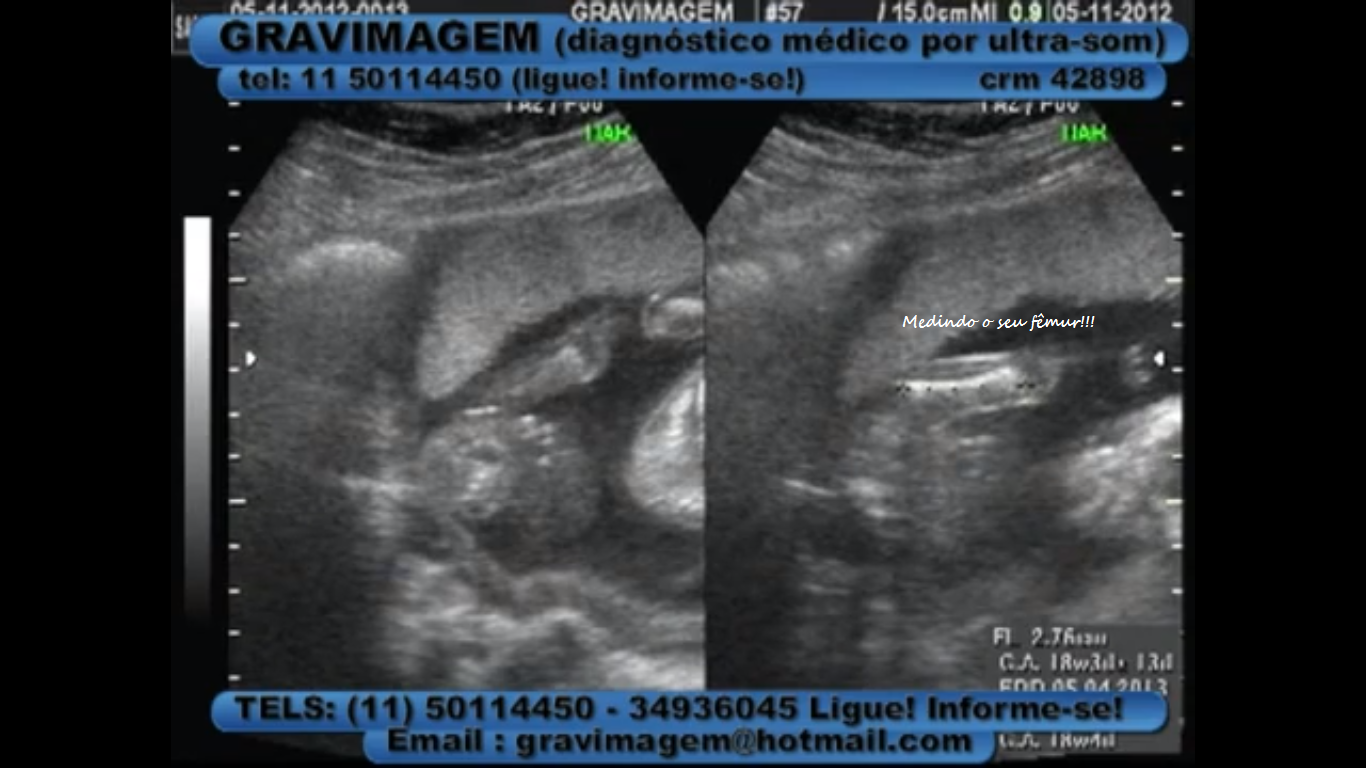

Olha aí as suas fotinhas com 19 semanas dentro da mamãe.

Ontem o médico disse que estava tudo bem com você, que está crescendo e engordando como deve ser.

Você está com cerca de 254 gramas e com 15 centímetros.

Seus lábios, a coluna, o crâneo, os ventrículos cerebrais laterais, o cordão umbilical,os rins, o estômago, o abdomen, o coração, a pele e a bexiga estão perfeitos e se desenvolvendo...

Seu coração agora bate a 175 bpm, e o meu nem se fala né... BATE duas vezes mais forte toda vez que sei que você está bem.